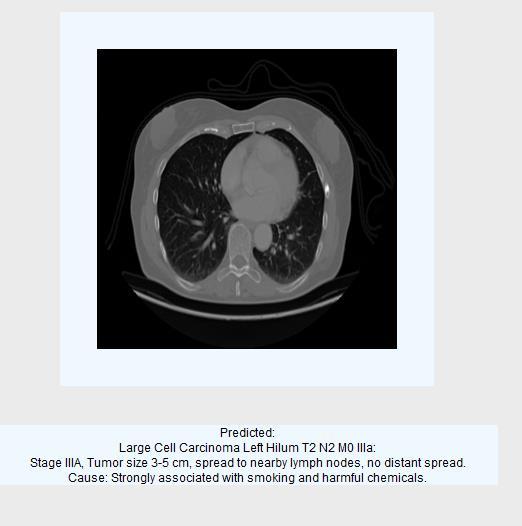

2.3.3Classification output images:

Fig8: Predictedascancercell-LargeCellCarcinoma